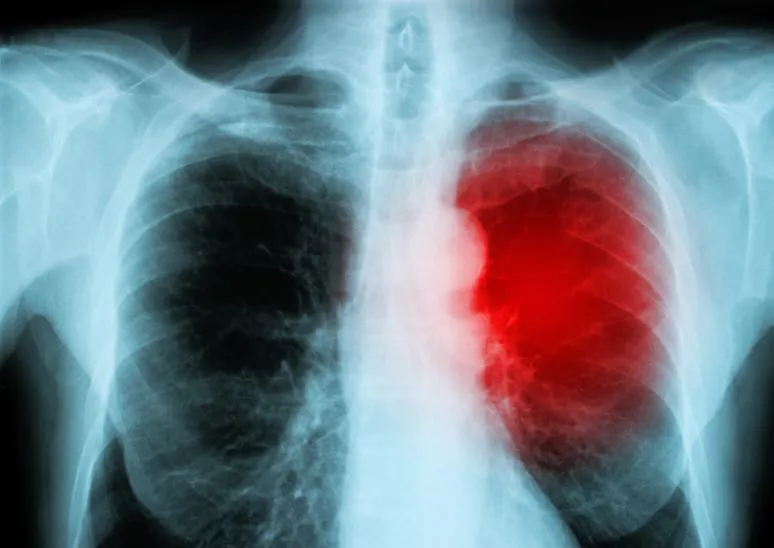

A medida que surge más información de la publicación ordenada por la corte de los documentos del ensayo clínico de Pfizer por parte de la FDA, y a través de correos electrónicos con FOIA, el encubrimiento por parte de los CDC de la evidencia de miocarditis asociada a la vacuna de ARNm COVID-19 en menores se vuelve cada vez más grave. La miocarditis es la inflamación del miocardio, que provoca la degeneración o necrosis de los tejidos.

Investigaciones posteriores realizadas por el difunto patólogo alemán Dr. Arne Burkhardt confirmaron que la miocarditis era causada por la inyección de ARNm: reveló la presencia de la proteína de pico en el miocardio de pacientes a los que se les había realizado una autopsia y que habían "muerto repentinamente", además de revelar cicatrices como resultado de los efectos autoinmunes.

Estos documentos contienen protocolos y hojas de "asentimiento" de información para un ensayo clínico pediátrico de la primavera de 2021 en el que Pfizer orquestó el SEGUIMIENTO ACTIVO, es decir, el seguimiento clínico y telefónico con los participantes a los cuatro días, un mes y seis meses, para evaluar el grado de daño cardíaco de la vacuna. (La hoja de "asentimiento" refleja un esfuerzo por permitir que el menor comprenda, en la medida en que sea capaz de hacerlo, lo que implicaría su participación en el proceso de toma de decisiones). Pfizer buscaba específicamente miocarditis.

Si bien la FDA y el Comité Asesor de Vacunas y Productos Biológicos Relacionados (VRBPAC, por sus siglas en inglés) reconocieron que la miocarditis es un riesgo importante identificado, esta es una discusión sobre los niños de cinco a 11 años, un grupo demográfico que no está en riesgo natural de padecer dicha afección cardíaca.

La miocarditis es normalmente un evento muy raro en niños de cinco a 11 años de edad y generalmente es causada por un agente infeccioso viral. A los CDC les preocupaba que los niños pequeños pudieran contraer miocarditis inducida por COVID, pero no entendían que las vacunas de ARNm contra la COVID estaban causando el daño cardíaco mediado por el sistema inmunitario en los niños, que se manifestaría después del breve ensayo, no durante el mismo.

Pfizer informó en el ensayo pediátrico de cinco a 11 años de antigüedad que no había casos de miocarditis. Sin embargo, la compañía solo realizó dos meses de seguimiento y hubo un pequeño número de sujetos vacunados (3.109). Si bien la miocarditis puede presentarse poco después de la vacunación, particularmente después de una segunda dosis, puede tomar mucho más de uno o dos meses para volverse sintomática hasta el punto en que el paciente se da cuenta de que se está produciendo un problema médico.

El formulario de consentimiento informado de Pfizer-BioNTech para la "Fase 2/3 de obtención de muestras de suero para posibles pruebas de troponina I" aconsejó a los padres de los participantes del ensayo que la miocarditis y la pericarditis son eventos adversos conocidos asociados con la vacuna COVID de ARNm de Pfizer y que deben buscar atención médica si su hijo sufre dolor en el pecho, dificultad para respirar, latidos rápidos, aleteo o palpitaciones cardíacas.

Al perpetuar la VIGILANCIA ACTIVA continua y las pruebas de los niveles de troponina I, Pfizer reconoció el riesgo de miocarditis y pericarditis inducidas por la vacuna y, por lo tanto, realizó pruebas adecuadas para detectar posibles enfermedades.